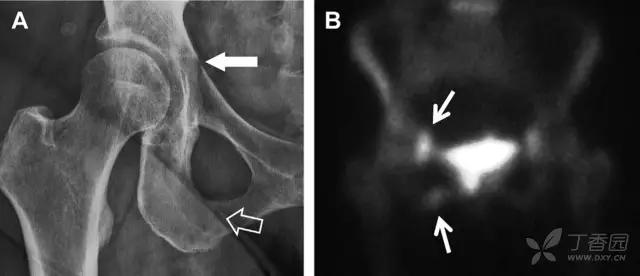

耻骨骨折

具有持续损伤因素的耻骨支骨折,可能看似轻微,尤其是合并骨质疏松的患者。因此,特别需要注意皮质缺损和骨密度改变。长跑运动员易发生耻骨应力性骨折,常常发生在靠近耻骨联合的下支。由于这些骨折为非移位骨折,所以常常被忽视。

图 3 自行车事故患者,侧方受力的髋臼前柱/耻骨骨折。A 正位平片示右侧髂耻线轻微中断(实箭头),此处异常最初并未发现。此外,右下方其实还有一处轻微耻骨支骨折(空箭头)。B 10 天后行骨闪烁显像证实了髋臼前柱骨折和侧耻骨下支骨折(箭头)。值得注意的是,左侧前柱亦存在异常